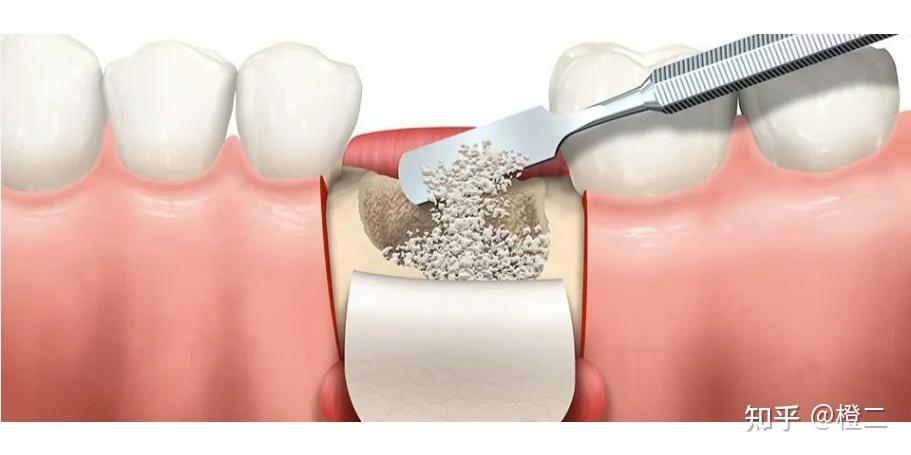

2、骨粉费用:种植牙的“隐藏成本”之前我也写过很多种植牙的文章,但很少聊到骨粉

简单说说:哪些人需要骨粉?牙槽骨高度<8mm或宽度<5mm

上颌窦底骨质薄需内提升

具体大家可以对照牙片来看,拿不准也可以私信问我(ps:我纯粹是为爱发电,打赏全关了的,不会收你一分钱,但我也有自己的工作,没办法秒回,看见就回哈)